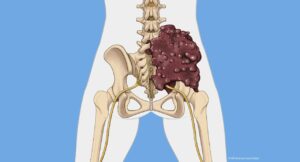

کوردوما این نوع نادر تومور استخوانی معمولاً در پایه جمجمه یا در استخوانهای تحتانی ستون فقرات ایجاد میشود. به طور کلی به کندی رشد می